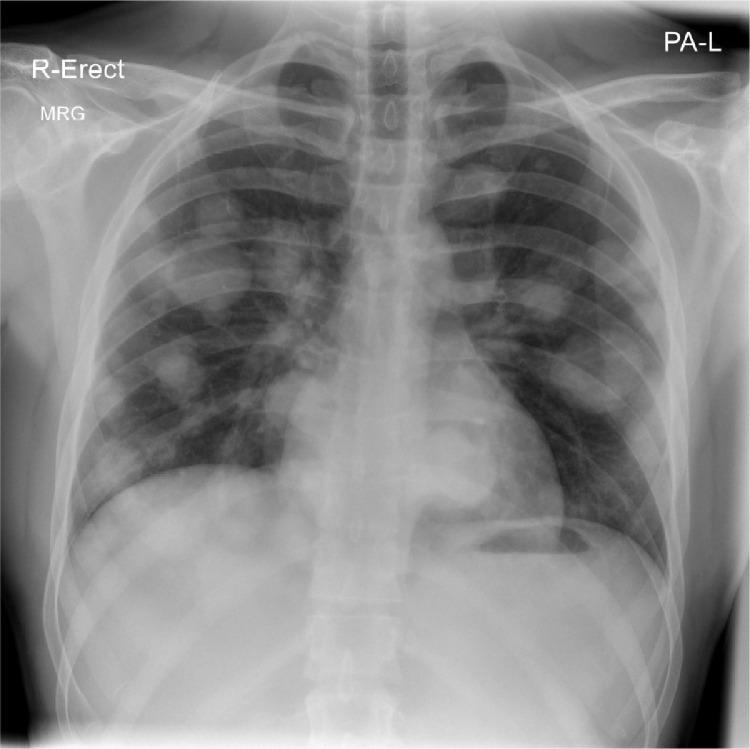

Pure testicular choriocarcinoma is an extremely rare subtype of nonseminomatous germ cell tumor, accounting for less than 1% of all germ cell tumors and only 0.19% of all testicular tumors. It is a highly aggressive malignant tumor with early multiorgan metastasis and poor prognosis. We present a case of 23-year-old male presented to the hospital with mild hemoptysis which was thought as a sequela of his past COVID-19 pneumonia infection, however; chest radiograph showed multiple rounded cannonball opacities seen throughout both lungs raising the suspicion of metastatic deposits to the lungs. During physical examination, left testicular painless swelling was noted leading to an ultrasound of the scrotum which revealed a left intratesticular infiltrative, heterogeneous mass. Tumor markers, including beta-human chorionic gonadotropin, lactate dehydrogenase and alpha fetoprotein were extremely high. Computed tomography scan of the brain, chest, abdomen, and pelvis showed hemorrhagic metastatic deposits to the brain, chest, and left para-aortic lymph nodes. The patient underwent radical orchiectomy and histopathology reports confirmed the diagnosis of pure testicular choriocarcinoma.

纯睾丸绒毛膜癌是一种极其罕见的非精原细胞瘤性生殖细胞肿瘤亚型,占所有生殖细胞肿瘤的比例不到1%,仅占所有睾丸肿瘤的0.19%。它是一种侵袭性很强的恶性肿瘤,早期多器官转移且预后较差。我们报告一例23岁男性患者,因轻度咯血入院,最初认为是既往新冠病毒肺炎感染的后遗症;然而,胸部X线片显示双肺多发圆形炮弹样阴影,怀疑有肺部转移灶。体格检查时,发现左侧睾丸无痛性肿大,遂行阴囊超声检查,结果显示左侧睾丸内有浸润性、不均匀肿块。包括β-人绒毛膜促性腺激素、乳酸脱氢酶和甲胎蛋白在内的肿瘤标志物极高。脑部、胸部、腹部和骨盆的计算机断层扫描显示脑部、胸部和左主动脉旁淋巴结有出血性转移灶。患者接受了根治性睾丸切除术,组织病理学报告确诊为纯睾丸绒毛膜癌。